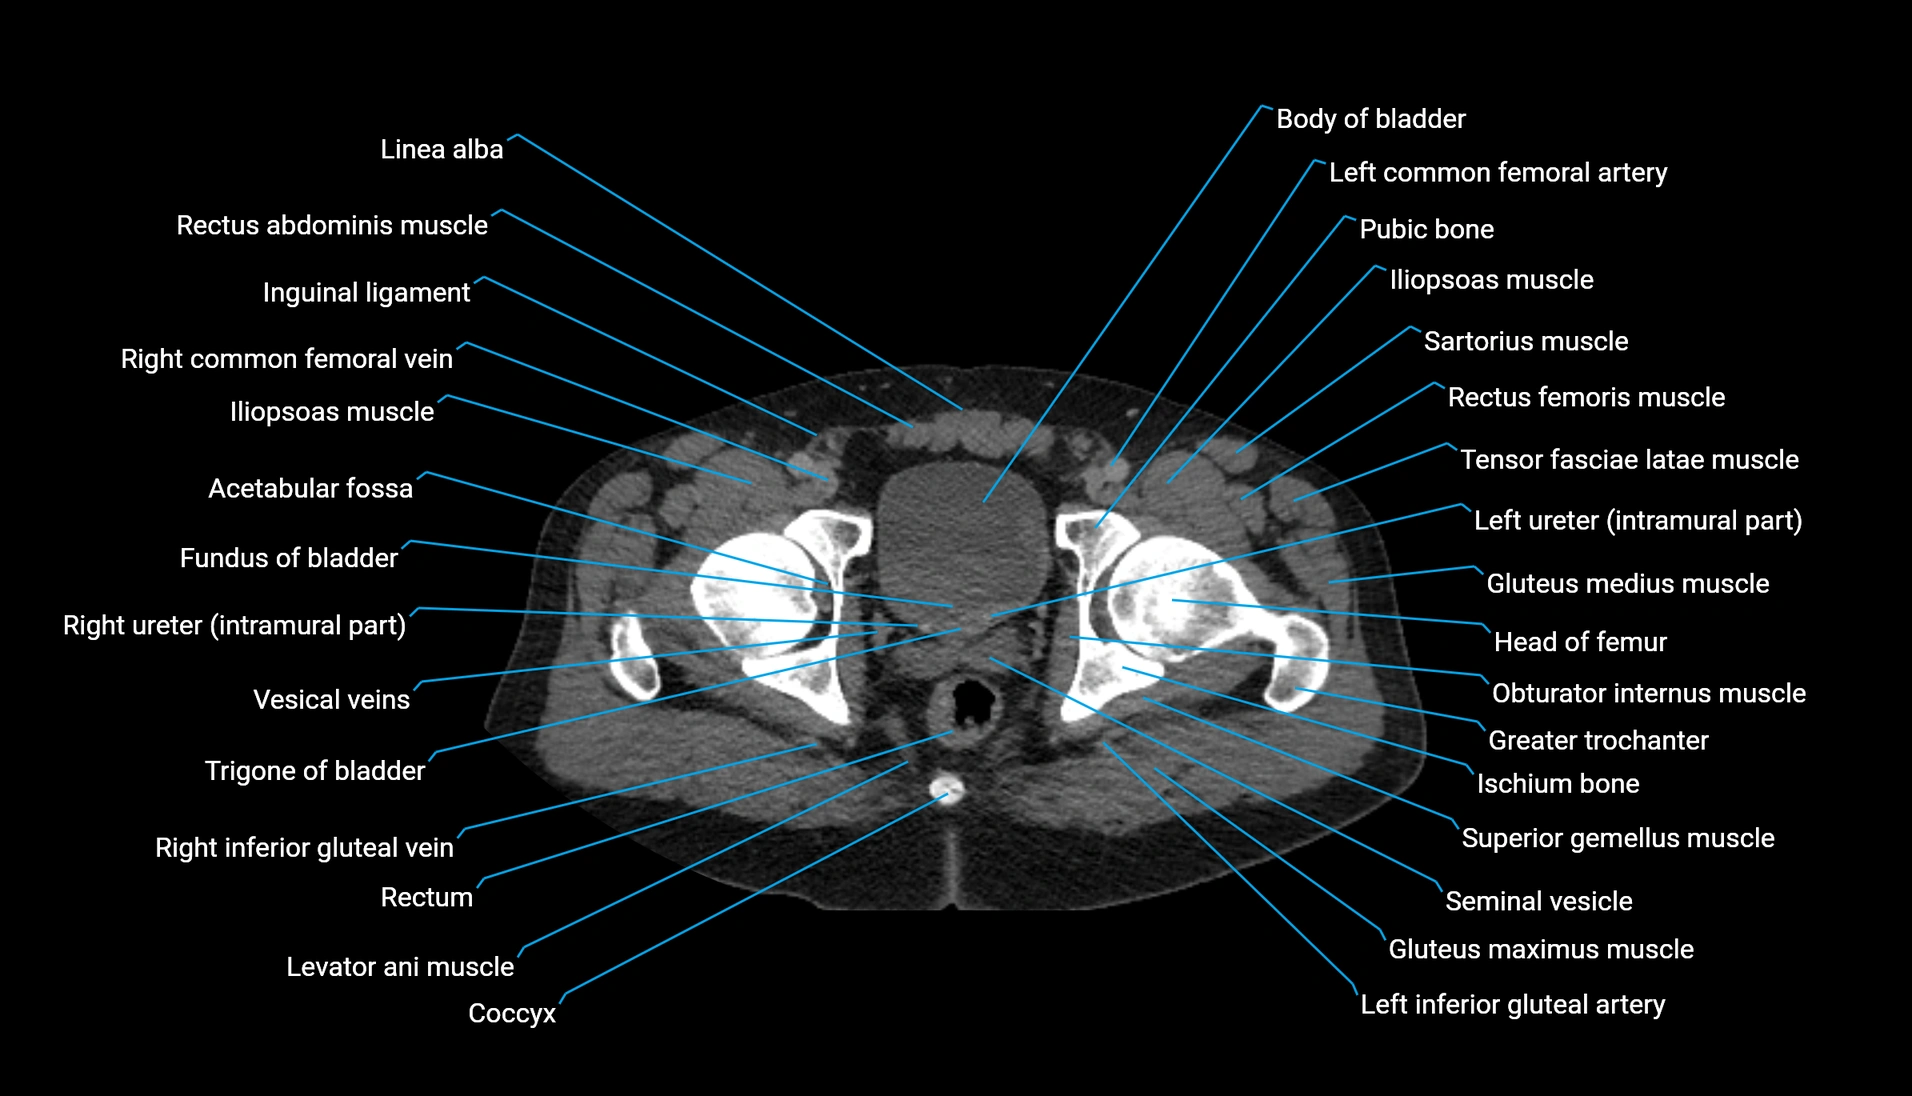

CT Appearance

Non-contrast CT:

-

Demonstrates cortical bone of acetabular rim in excellent detail

Detects fractures, dysplasia, retroversion, or bony overcoverage (pincer impingement)

3D reconstructions used in preoperative hip surgery planning

CT VRT 3D image

CT image